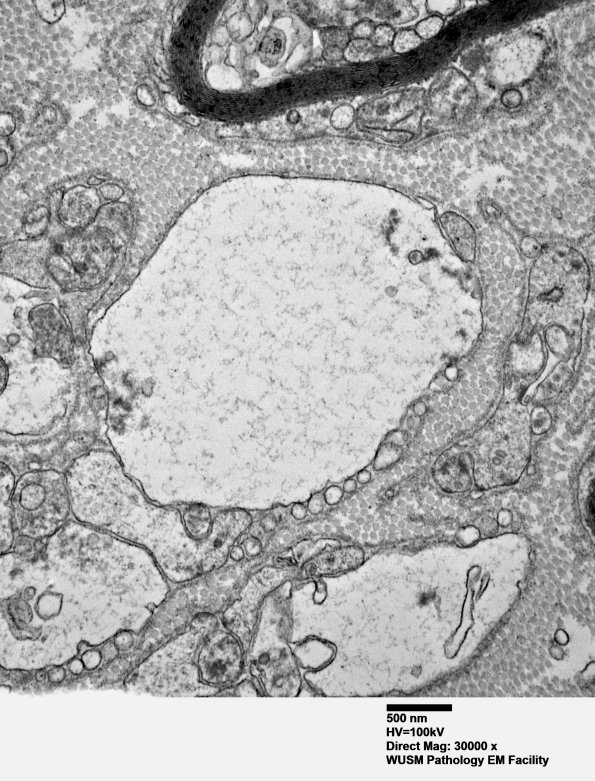

This appears to represent a degenerating immature axon but I am not certain (electron micrograph)